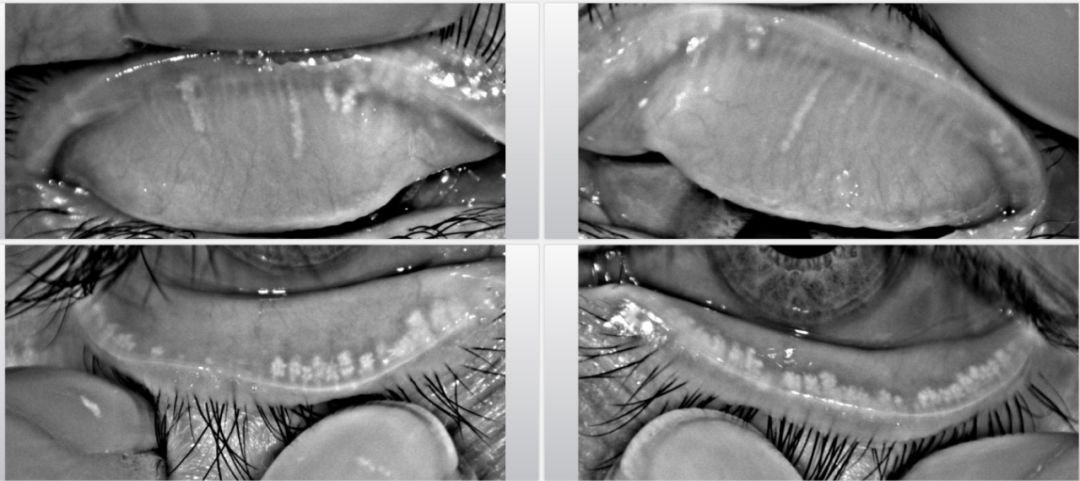

(圖一)正常的睑闆腺

(圖二)中度睑闆腺缺失